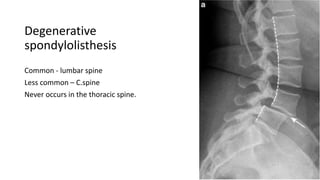

Degenerative

spondylolisthesis

Common - lumbar spine

Less common – C.spine

Never occurs in the thoracic spine.

Degenerative spondylolisthesis Common - lumbarspine Less common – C.spine Never occurs in the thoracic spine.